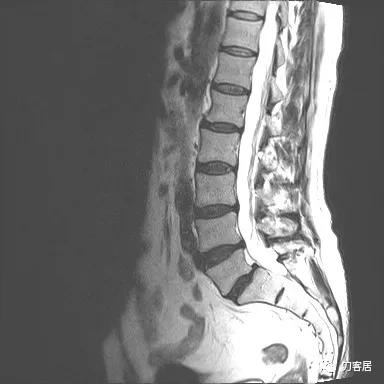

图13. 20210626术前腰椎MRIT1相1

图14. 20210626术前腰椎MRIT1相2

入院后予以腰椎CT及MRI检查,未见明显之椎间盘突出及椎管狭窄。